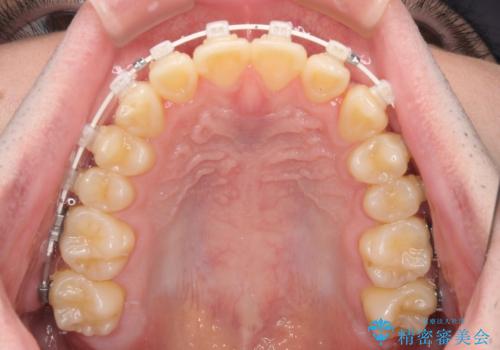

- 矯正装置

- 審美装置

- 1年1ヶ月

インビザラインでもワイヤー装置でも矯正治療は可能でしたが、煩わしい自己管理なしに短期間で治療を行いたいとのことで、目立たないワイヤー装置にて治療を行うこととしました。